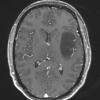

NEOPLASMS (GLIAL)

Astrocytoma, IDH-mutant, WHO Grade 2 (8)